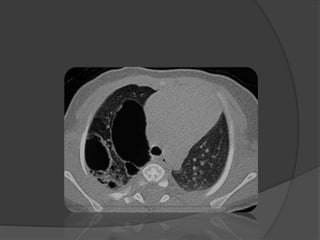

Imagerie: TDM

• Confirme le dg si doute

• Élimine les dg différentiels

• Précise le type, la topographie

Imagerie: TDM • Confirmele dg si doute • Élimine les dg différentiels • Précise le type, la topographie